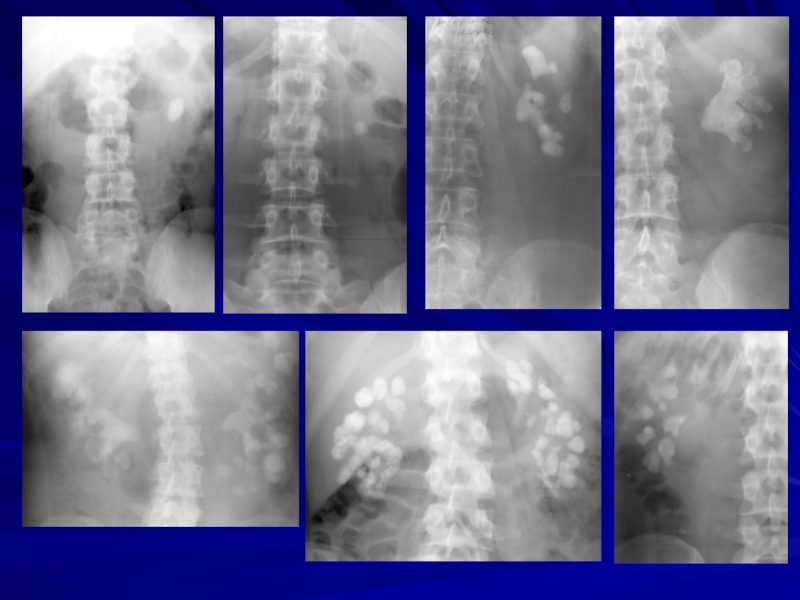

МСКТ с мультипланарной реформацией,

3D реконструкцией

и виртуальной эндоскопией

Слайд 24МСКТ при рентгеннегативных камнях

Слайд 25Возможности МСКТ

Мультипланарные построения (МПР) обеспечивают визуализацию камней мочевой системы в любой

интересующей плоскости1.

Возможно измерение КТ-плотности конкрементов в единицах Хаунсфилда (HU), что помогает выбрать оптимальный метод лечения2.